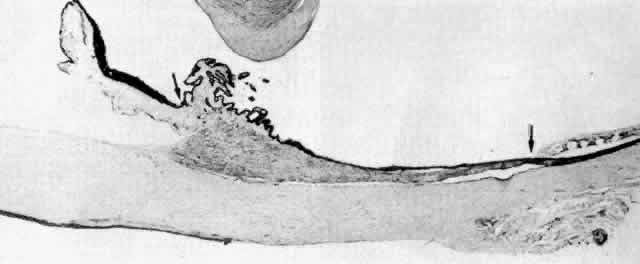

Fig. 30. Pars plicata of the ciliary body cut coronally, perpendicular to the usual

plane. Ciliary muscle (CM) does not extend into the ciliary processes, but

has the same thickness under processes and valleys. The anterior

hyaloid membrane is visible above the processes (arrowheads). (hematoxylin-eosin, X 120) Fig. 30. Pars plicata of the ciliary body cut coronally, perpendicular to the usual

plane. Ciliary muscle (CM) does not extend into the ciliary processes, but

has the same thickness under processes and valleys. The anterior

hyaloid membrane is visible above the processes (arrowheads). (hematoxylin-eosin, X 120)

|